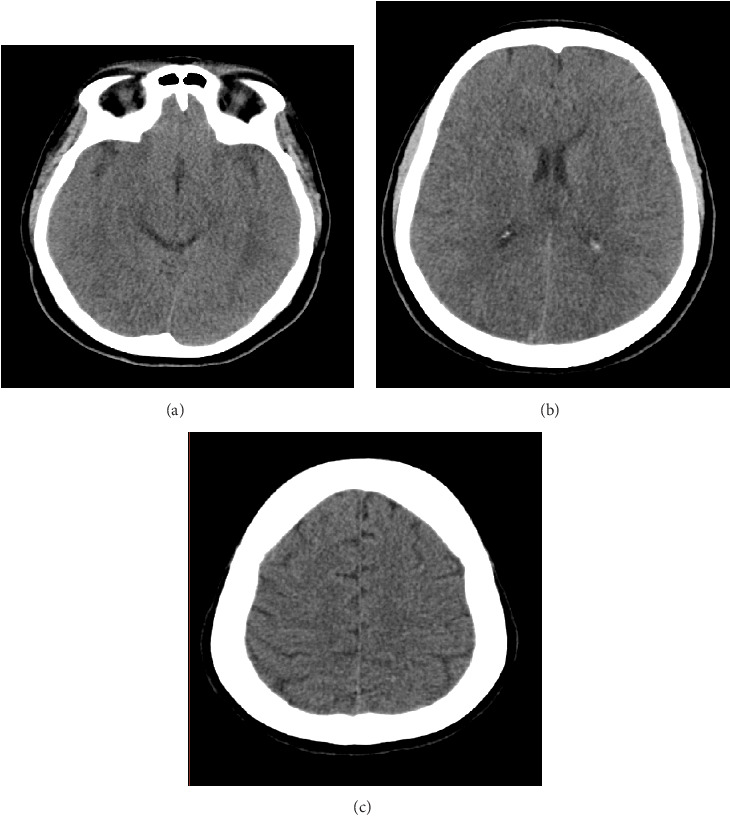

目的:探讨眼周填充物注射对脑静脉血栓形成(CVT)的影响。病例报告:一名没有既往病史的41岁女性在眼部填充物注射后出现严重头痛和随后的癫痫发作。通过脑磁共振静脉造影(MRV)证实CVT的诊断,显示左横窦和上矢状窦血栓形成。患者经静脉滴注肝素及口服华法林治疗,住院10天后病情好转出院。结论:本病例强调了眼周填充物注射后CVT的潜在风险,强调了医务人员认识和预防措施的必要性。

Purpose: To evaluate the effect of periocular filler injection on the incidence of cerebral venous thrombosis (CVT). Case Report: A 41-year-old woman without a prior medical history experienced a severe headache and subsequent seizures following an eye filler injection. Diagnosis of CVT was confirmed through brain magnetic resonance venography (MRV), revealing thrombosis in the left transverse and upper sagittal sinuses. The patient was treated with intravenous heparin and oral warfarin, leading to improvement and discharge in good condition after 10 days of hospitalization. Conclusion: This case underscores the potential risk of CVT following periocular filler injections, emphasizing the need for awareness and preventive measures among medical professionals.